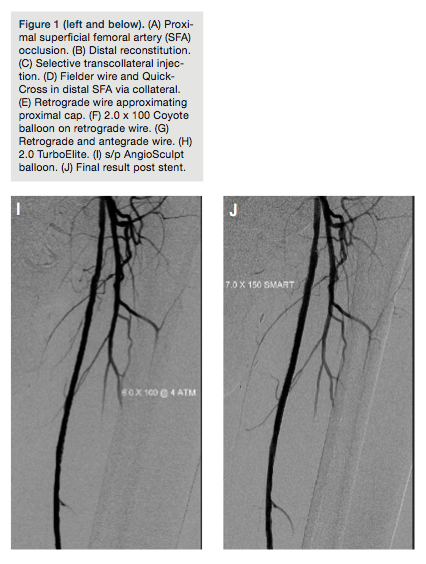

The right common femoral artery was accessed using a 4 French (Fr) micropuncture kit (Cook Medical).The sheath was upsized to a 5 Fr Avanti sheath (Cordis Corporation); using a 5 Fr IMA catheter (Boston Scientific) and an exchange-length Glidewire (Terumo Corporation), the catheter was advanced into the left common femoral. The sheath was then upsized to a 6 Fr, 45 cm Pinnacle Destination sheath (Terumo Corporation) placed in the origin of the left SFA. After administration of heparin, an Asahi Miracle Bros 6 wire (Abbott) was advanced to the cap. A Wildcat catheter (Avinger) was then advanced over the wire distally. An attempt to engage the cap resulted in deflection of the Wildcat into the collateral. Several attempts were made using the back end of the wire advanced to the distal tip of the catheter to provide more support while utilizing the Wildcat in different modes. Repeated attempts resulted in advancement of the device into the collateral branch. Next, an angled 0.18˝ QuickCross Extreme (Spectranetics) was used with a Treasure 12 guidewire (Abbott). Multiple attempts were made to advance the Treasure 12 wire into the proximal cap. It was felt this might allow advancement of the Wildcat to the cap without concern of deflecting into the collateral. Unfortunately, the proximal cap could not be penetrated secondary to the calcium as well as the angle and presence of a collateral. At this point, consideration was given to using an angled Glidewire and QuickCross catheter, and attempt a subintimal approach or bring the patient back for popliteal access. After further examination of the angiograms and angulated views (ipsilateral 20°), it was felt that there was an adequate collateral to attempt transcollateral passage of a wire. The Destination sheath was withdrawn into the left common femoral, and the wire was advanced into the collateral utilizing a Runthrough wire (Terumo) and a Finecross catheter (Terumo). Due to poor visualization of the catheter, the Finecross was exchanged for a 0.14˝ QuickCross and the wire was exchanged for a 300 cm Asahi Fielder wire (Abbott). Selective injection was then performed of the collateral through the QuickCross (Figure 1C). The Fielder wire was negotiated through the collateral and into the distal lumen of the SFA (Figure 1D). The 0.14˝ QuickCross was then advanced into the SFA in a retrograde manner and the wire was changed to an Asahi Confienza wire (Abbott). The wire was advanced in a retrograde manner through the calcified lesion to the proximal cap (Figure 1E). The cap could not be penetrated, despite attempts with several wires (Confienza, Cross-It, Pilot 300). At this time, the 0.14˝ QuickCross was exchanged for an 0.18˝ QuickCross through the collateral in a retrograde manner. The wire was then changed to a Treasure 12 wire, which easily penetrated the cap. The wire was then advanced into the left common femoral artery and exchanged for a Runthrough wire. Several attempts were made to rewire the sheath or rewire an angled catheter. This was in order to externalize the wire and proceed with revascularization. These attempts were unsuccessful. Multiple attempts were made to snare the wire by utilizing a 2.0 mm loop snare (eV3). This also was unsuccessful. At this point a 2.0 x 100 Coyote balloon (Boston Scientific) was advanced via the collateral into the lesion in a retrograde manner. The vessel was dilated at 6 atm for 20 seconds (Figure 1F). At this point, a Fielder wire was easily advanced in an antegrade manner into the tibioperoneal vessel and then exchanged for a RunThrough wire (Figure 1G). A 2.0 TurboElite Laser fiber (Spectranetics) was then utilized to debulk and modify the plaque as well as facilitate balloon delivery (Figure 1H). The lesion was

predilated with a 6.0 x 100 AngioSculpt scoring balloon (AngioScore) at 4 atm x 2 minutes (Figure 1I). This was performed in an overlapping manner. This was then followed by placement of a 7.0 x 150 SMART stent (Cordis), which was postdilated with a 7.0 x 100 Sterling balloon (Boston Scientific) at 4 atm (Figure 1J). Final angiography demonstrated brisk flow without embolization, perforation, or dissection. The sheath was withdrawn and a Mynx closure (AccessClosure) was performed in the right groin. The patient was discharged home the following morning without incidence.